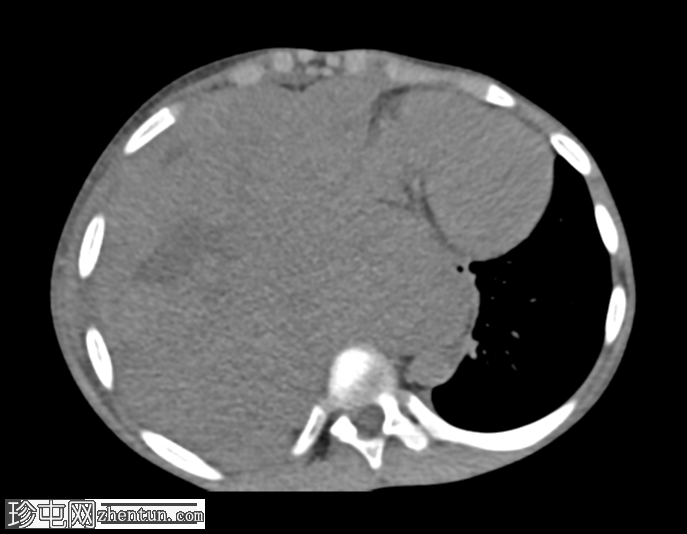

CT 发现:

一个大的、不均匀强化的肿块占据整个右半胸腔,导致右肺几乎完全塌陷。肿块延伸至纵隔,导致观察到的纵隔移位。病灶内未见钙化。此外,右侧第三和第八肋骨后方可见轻微骨膜反应。